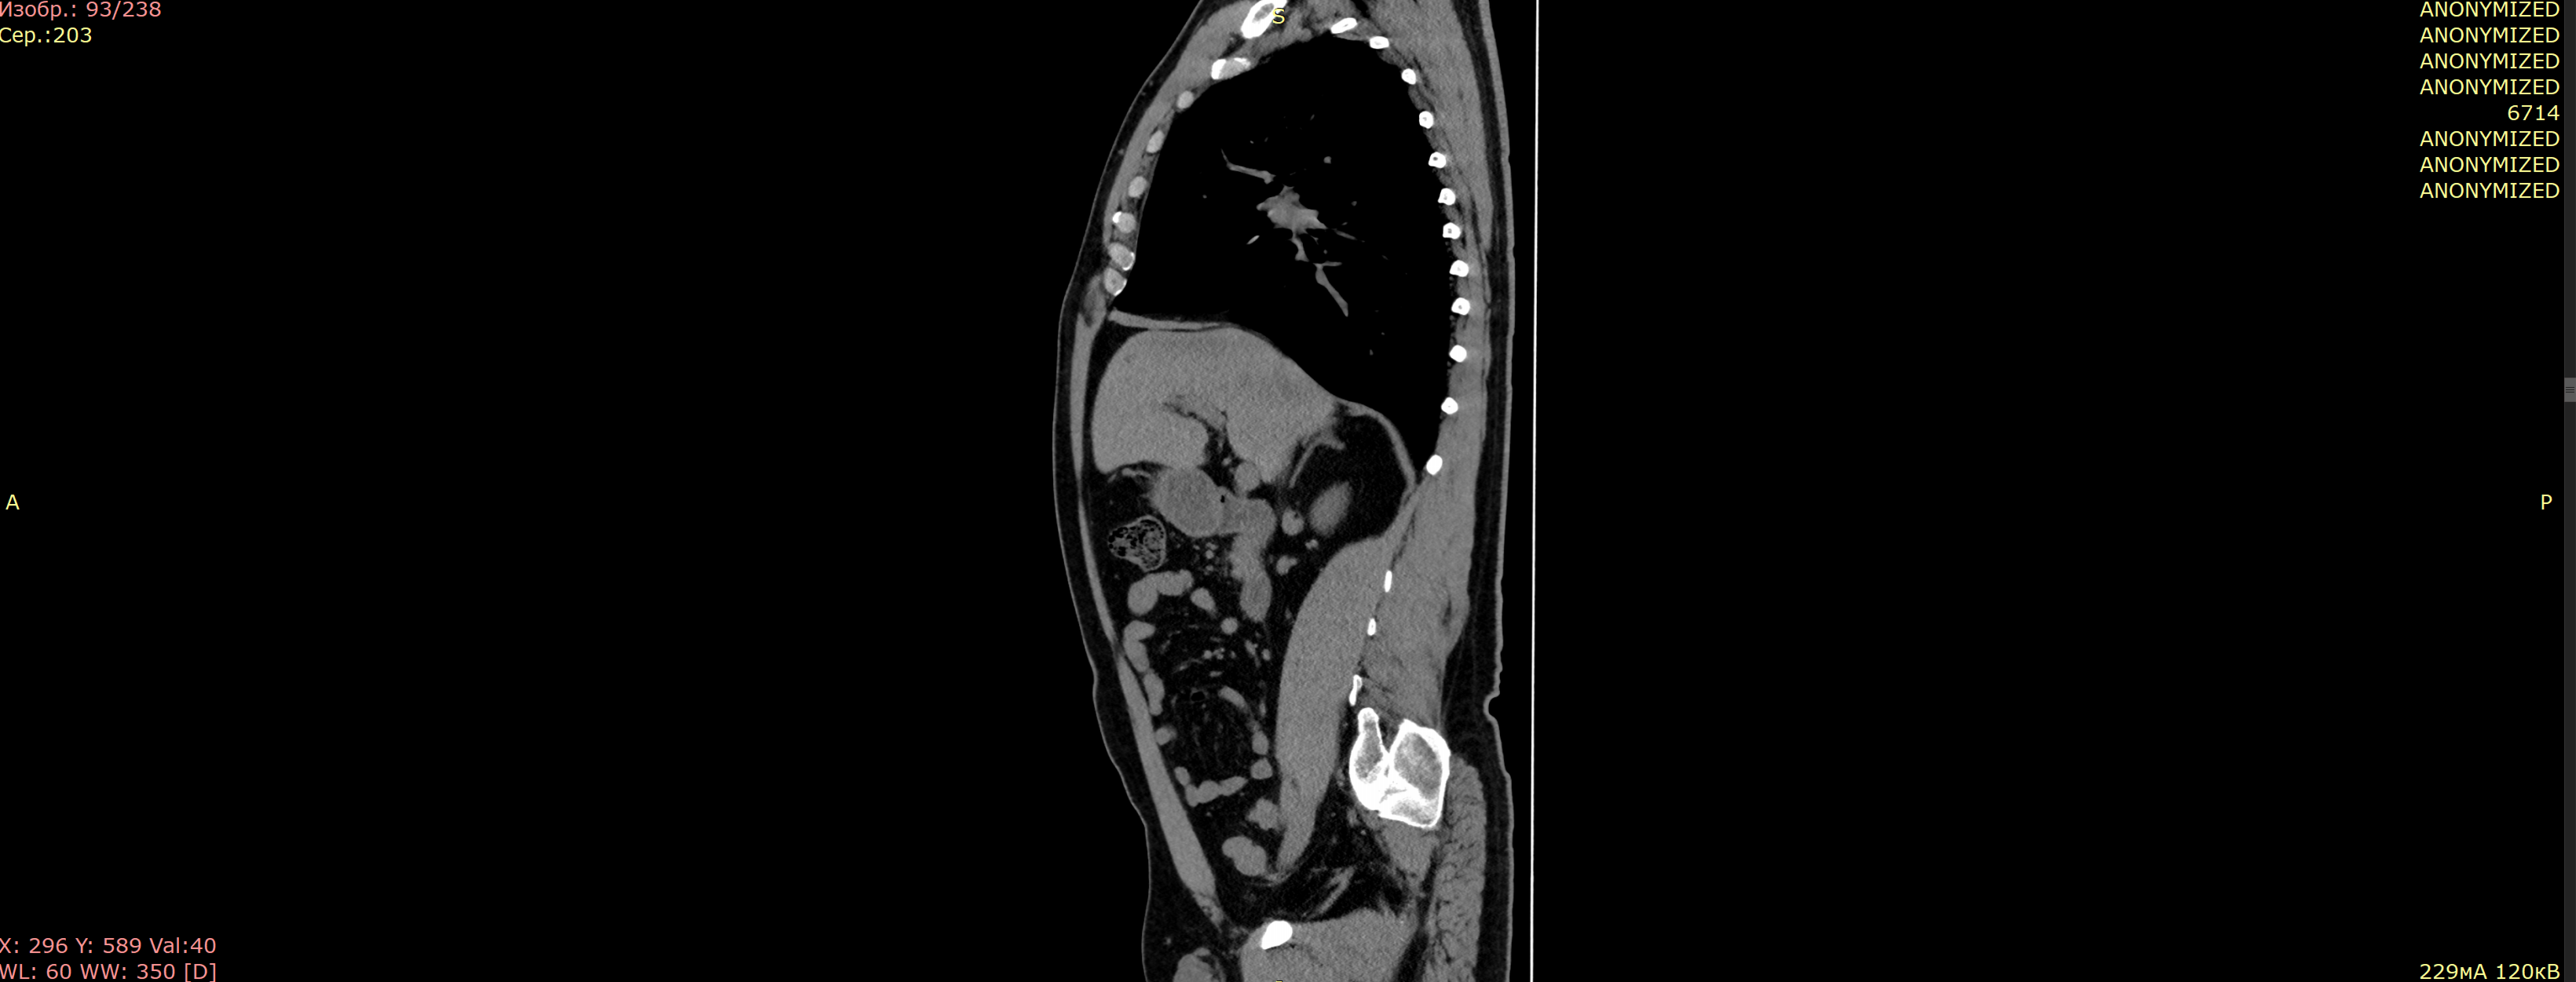

Компьютерная томография органов брюшной полости

Скачать отчет (oncological segmentation)

Результат анонимизации DICOM

🖼️ Пример анонимизированного файла

Пример анонимизации DICOM

Все персональные данные заменены на "ANONYMIZED"